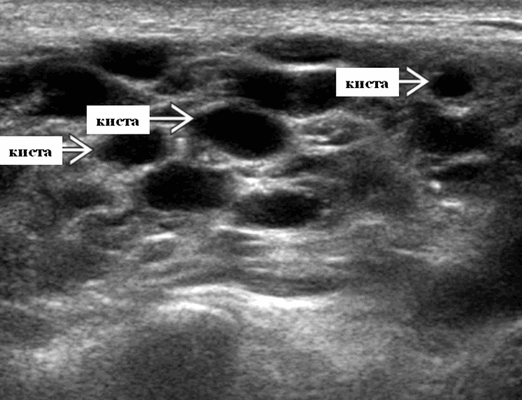

Определение. Мультифокальные смешанные кистозные и солидные интрапаротидные образования, обнаруженные у ВИЧ-инфицированных пациентов.

3-х уровневая классификация. Кистозные поражения: кисты ДЛК. Смешанные солидные и кистозные образования: ДЛП. Солидные поражения: стойкая генерализованная лимфаденопатия околоушных желез.

Ультразвуковое исследование слюнных желез. Общие особенности

Лучший диагностический признак: множественные кистозные и твердые образования, увеличивающие обе околоушные железы, связанные с гиперплазией миндалин и реактивной аденопатией шеи

Расположение. Двустороннее вовлечение околоушных слюнных желез на УЗИ. Редко наблюдается в подчелюстных или подъязычных слюнных железах. Только околоушная железа имеет собственную лимфоидную ткань.

Размер. Переменный: обычно несколько мм, ≤ 3,5 см

Морфология. Кисты хорошо очерчены, округлой формы. Солидные лимфоидные агрегаты могут быть плохо определены. Часто бесчисленные маленькие массы; необычно одинокий

- Серошкальное УЗИ. Спектр сонографических находок от простых кист до смешанных и солидных образований. Кистозные, смешанные и солидные поражения могут возникать одновременно в околоушных железах. Кистозные поражения (кисты ДЛК). Хорошо очерченная киста, разного размера, от анэхогенной до гипоэхогенной структуры с задним акустическим усилением. Сеть тонких перегородок ± муральные узлы. Часто встречаются внутренние эхо, которые могут быть мобильными. Сотовидная внешность паренхимы околоушной железы, когда она диффузно изменена з а счет кист. Смешанные поражения (ДЛП). Границы могут быть плохо очерченными, разного размера. Структура преимущественно гипоэхогенная, железы могут быть неоднородными. Без заднего акустического усиления. Солидные поражения (околоушная лимфаденопатия). Множественные овальные / круглые, гипоэхогенные, внутрипаротидные лимфоузлы на УЗИ. Четкий корковый слой ± сохранная корневая архитектура. Сопутствующая реактивная шейная лимфаденопатия